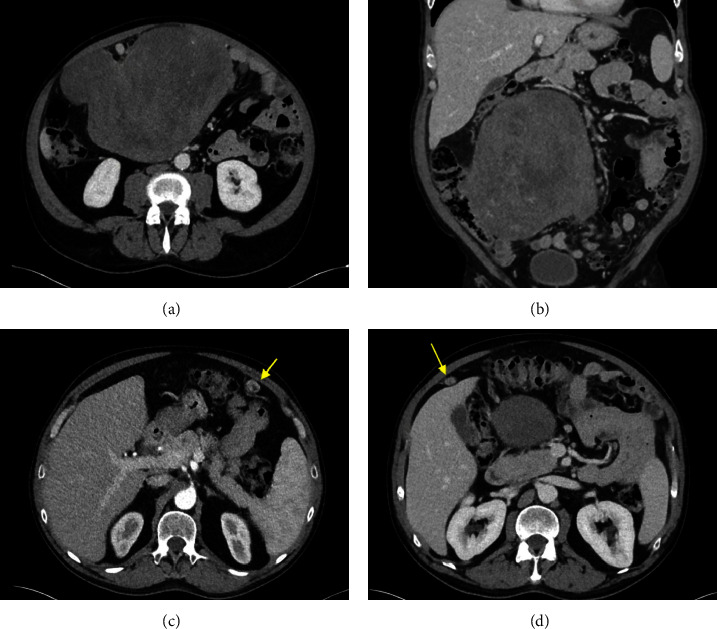

非胰岛细胞肿瘤性低血糖症(NICTH)是一种与大型间质肿瘤相关的罕见临床症状。其发病机制最常见的是肿瘤过量分泌 "大 "胰岛素样生长因子-2。在此,我们介绍一名 54 岁的男性患者,他出现了非胰岛素介导的低血糖症,腹腔内有一个 20 厘米长的子宫肌瘤。肿瘤切除后,他的低血糖症状缓解。据我们所知,这是英文文献中唯一一例男性患者伴有子宫肌瘤的 NICTH 病例。对于任何伴有低血糖和腹部肿块的患者,良性子宫肌瘤引起的 NICTH 都应列入鉴别诊断范围。

Non-islet cell tumor hypoglycemia (NICTH) is a rare clinical entity associated with large mesenchymal tumors. Its pathogenesis is most commonly mediated by tumor overproduction of "big" insulin-like growth factor-2. Here, we present a 54-year-old male who presented with noninsulin-mediated hypoglycemia and a 20 cm intra-abdominal leiomyoma. His hypoglycemic episodes resolved after the resection of his tumor. To our knowledge, this is the only documented case in the English literature of NICTH associated with leiomyoma in a male patient. NICTH due to a benign leiomyoma should be in the differential diagnosis for any patient with hypoglycemia and an abdominal mass.